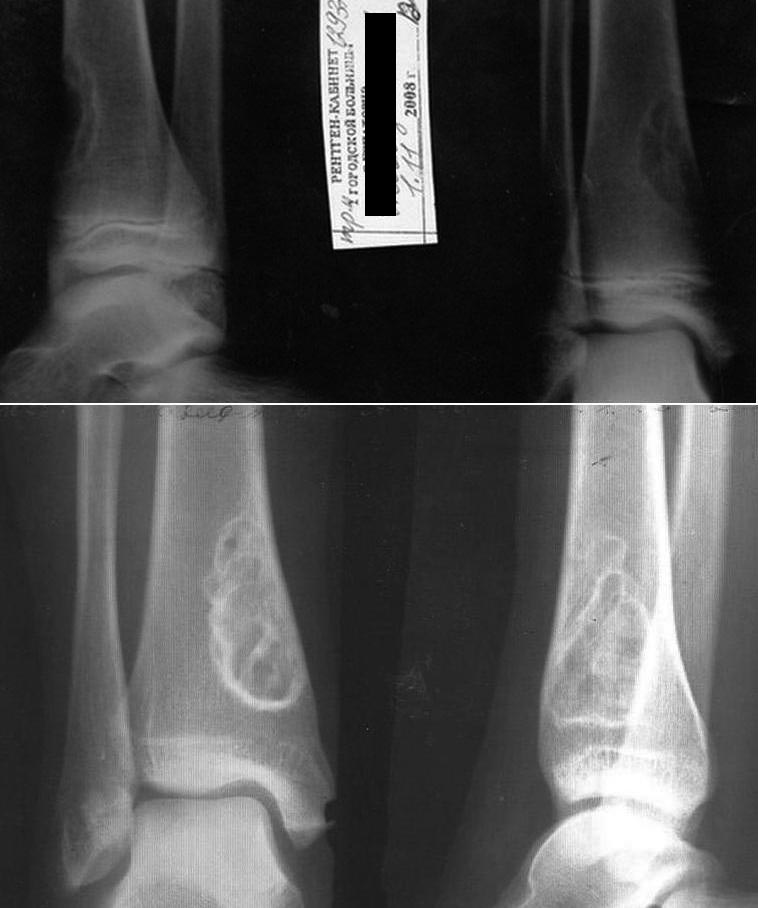

Прошу консультацию по тактике лечения солитарной кисты большеберцовой кости.

Девочка 17 лет, в 2008 году появились боли в области большеберцовой кости.

Выполнена рентгенограмма (верхняя) и рекомендовано наблюдение.

Вновь боли появились в 2012 году выполнена рентгенограмма (нижняя) и остеосцинтиграфия.

15.11.2012. Cцинтиграфия костей голеней, стоп:

регистрируется повышенное накопление РФП в нижней трети правой большеберцовой кости размерами 4х3 см, без четких контуров - 180% (по сравнению с симметричной зоной левой голени).

Заключение. Сцинтиграфические данные умеренно выраженного остеобластическогом процесса нижней трети правой большеберцовой кости.

Непохоже на кисту.

Несмотря на увеличение размеров образования в динамике, имеется положительная динамика. На раннем снимке больше данных за метафизарный фиброзный дефект, а на позднем - это неоссифицирующая фиброма с признаками спонтанной оссификации. Болевой синдром возможно был обусловлен нагрузками или двигательной активностью. Угроза патологического перелома маловероятна при соблюдении разгрузочного режима (исключить бег, прыжки). Возможно динамическое наблюдение.